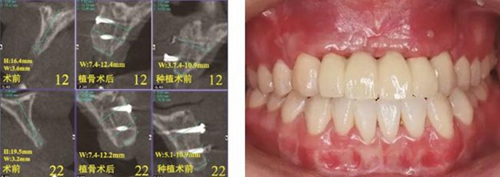

(1)2014年1月:初診明確診斷為12、11、21、22缺失,缺牙區(qū)牙槽嵴較薄,拍攝CBCT(kavo卡瓦,德國)顯示:缺牙區(qū)存在水平向骨缺損,12位點(diǎn)可用牙槽骨高度為16.4mm,寬度為3.6mm;22位點(diǎn)可用牙槽骨高度為19.5mm,寬度為3.2mm,唇側(cè)骨板稍有凹陷,明確治療計(jì)劃。

夠骨面,使用骨鑿等取骨器械制取骨塊,填塞明膠海綿,分層縫合??趦?nèi)切開植骨區(qū)粘膜,翻瓣,充分暴露待植骨區(qū),用裂鉆在受骨區(qū)骨面預(yù)備若干滋養(yǎng)孔,修整骨塊,以器械夾持骨塊置于手術(shù)受植骨區(qū)并緊貼骨床,使用鈦釘牢固地固定骨塊,植骨塊間的間隙用自體骨屑及少量骨粉(Geistlich Bio-Oss,瑞士)混合后充填,充分減張后嚴(yán)密縫合創(chuàng)口。告醫(yī)囑,囑患者術(shù)后幾天盡量臥床休息,十天后拆線。拍攝CBCT示:牙槽嵴寬度擴(kuò)增明顯:12位點(diǎn)擴(kuò)增至7.4mm-12.4mm,22位點(diǎn)擴(kuò)增至7.4mm-12.2mm。

圖3 術(shù)前測量12骨量 圖4 術(shù)前測量22骨量

圖17 CBCT測量骨量變化 圖18 早期修復(fù)戴牙當(dāng)天